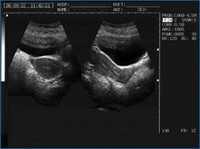

Galería de Imágenes Clínicas

Sonolife 9618